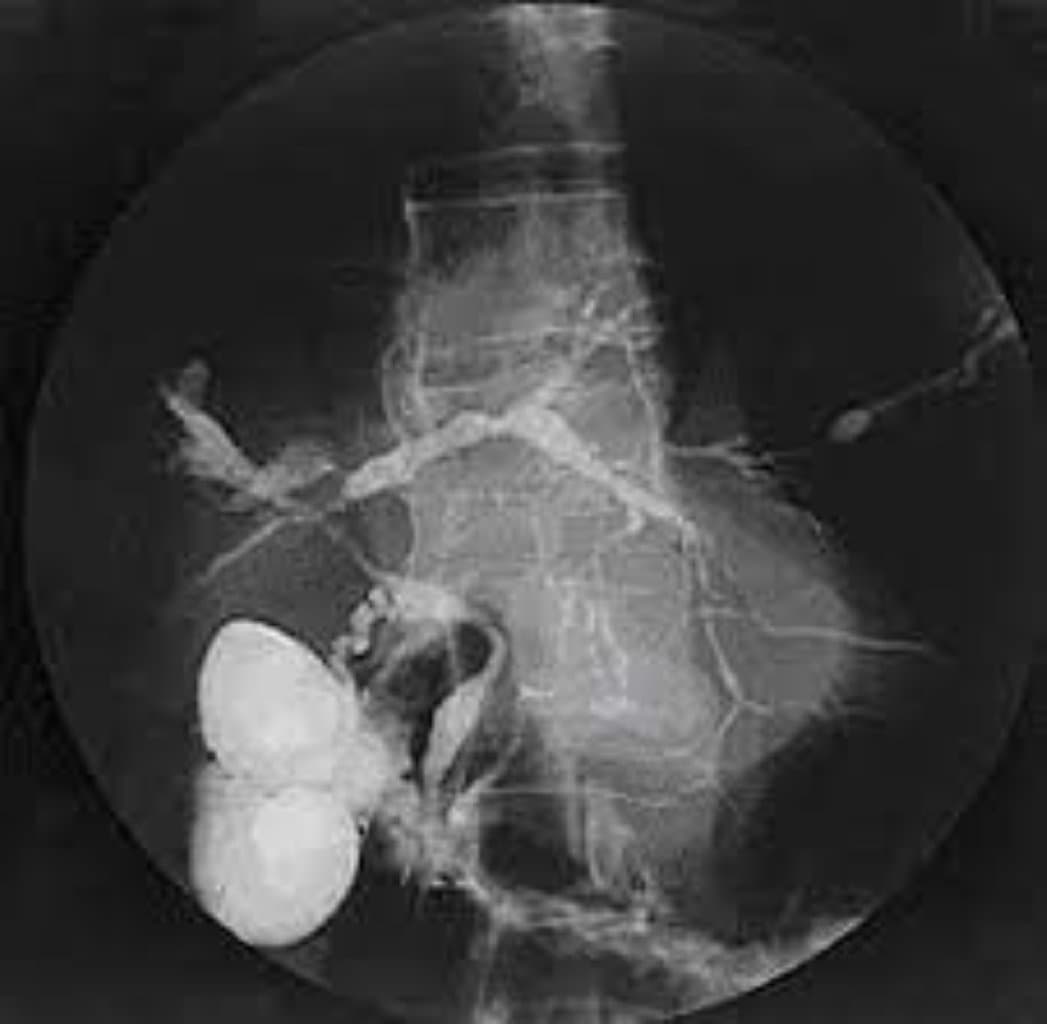

| Görüntüləmə (MRCP/ERCP) | Öd yollarının strukturunu vizuallaşdıran xüsusi radioloji müayinələr |